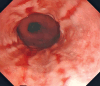

Combining transoral fundoplication and robotic cruroplasty: a novel robotic-assisted endoscopy